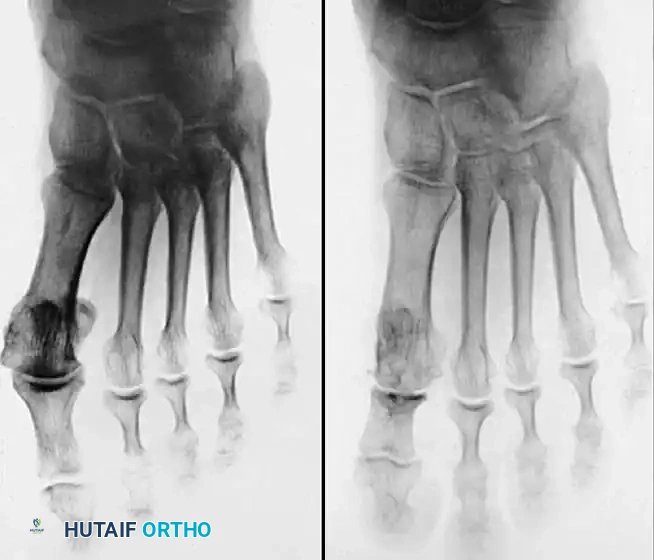

Hallux valgus (lateral deviation of the great toe) is not a single disorder, as the name implies, but a complex deformity of the fi rst ray that frequently is accompanied by deformity and symptoms in the lesser toes (Fig. 78-1). Often the angle between the fi rst and second metatarsals is more than the 8 to 9 degrees usually considered to be the upper limits of normal. The valgus angle of the fi rst metatarsophalangeal joint also is more than the 15 to 20 degrees considered to be the upper limits of normal (Fig. 78-2). If the valgus angle of the fi rst metatarsophalangeal joint exceeds 30 to 35 degrees, pronation of the great toe usually results. With this abnormal rotation, the abductor hallucis, which is normally plantar to the fl exion-extension axis of the fi rst metatarsophalangeal joint, moves further plantarward (Fig. 78-3). In this case, the only restraining medial structure is the medial capsular ligament with its capsulosesamoid portion (inserting into the base of the proximal phalanx) (Fig. 78-4) and capsulophalangeal portion (inserting into the plantar plate). The adductor hallucis, which is unopposed by the abductor hallucis, pulls the great toe further into valgus, stretching the medial capsular ligament (particularly the capsulosesamoid), attenuating this structure, and allowing the metatarsal head to drift medially from the sesamoids. In addition, the fl exor hallucis brevis, fl exor hallucis longus, adductor hallucis, and extensor hallucis longus increase the valgus moment at the metatarsophalangeal joint, further deforming the fi rst ray. The deep transverse intermetatarsal ligament runs between the plantar plates at the metatarsophalangeal joints and does not insert into bone on the adjacent sides of the metatarsal heads. Finally, the sesamoid ridge on the plantar surface of the fi rst metatarsal head (the crista) fl attens because of pressure (abutment) from the tibial sesamoid (Fig. 78-5). With this restraint lost, the fi bular sesamoid displaces partially or completely into the fi rst intermetatarsal space (see Fig. 78-2). In this situation, the patient is bearing less weight on the fi rst ray and more on the lesser metatarsal heads, increasing the likelihood of transfer metatarsalgia, callosities, and stress fracture of a lesser metatarsal.

Fig. 78-2 Hallux valgus complex. Note increase in intermetatarsal angle, lateral dislocation of sesamoids, subluxation of fi rst metatarsophalangeal joint (leaving metatarsal head uncovered), and pronation of great toe associated with marked hallux valgus.

Two other anatomical variants involving the articular surface of the fi rst metatarsophalangeal joint can lead to hallux valgus. In the fi rst variant, the articular surface of the metatarsal head is offset, resembling a scoop of ice cream sitting at an angle on a cone (Fig. 78-6). This has been described as the distal metatarsal articular angle (see Fig. 78-8). In the second, the articular angle of the base of the proximal phalanx in relation to its longitudinal axis is offset. This has been described as the phalangeal articular angle. Although the normal range of these angles is generally considered to be 7 to 10 degrees for the phalangeal articular angle and 10 to 15 degrees for the distal metatarsal articular angle, exact measurements are diffi cult to reproduce because of the variability of radiographic and measurement techniques. Increasing evidence indicates, however, that the failure to correct these two deformities, especially the distal metatarsal articular angle, can cause unsatisfactory results after surgery in some patients. Forceful straightening of the hallux should be avoided if it sacrifi ces tarsalgia. The entire forefoot must be evaluated for these multiple components of hallux valgus before surgical planning is complete and recommendations can be made to the patient. The controversy continues over which deformity is the essential lesion in hallux valgus: metatarsus primus varus or lateral deviation of the great toe. Each is incriminated as the cause of the other. The strongest data probably support lateral deviation of the great toe as the primary deformity in most patients, followed by medial angulation of the fi rst metatarsal, but metatarsus primus varus may be the principal cause in adolescents. Further controversy surrounds the role of footwear as the prime offender in the development of hallux valgus. Most orthopaedic surgeons have seen unilateral hallux valgus when both feet are clinically and radiographically the same structurally except that one foot has a bunion deformity and the other foot is normal. Evidence supports that hallux valgus may be familial, especially when it occurs in adolescents. Although no study of shod and unshod societies has implicated inappropriate footwear as the sole cause of hallux valgus, after genetic factors, binding, unphysiologically designed footwear probably is the major cause in modern societies. Hypermobility of the fi rst ray also has been suggested as a causative factor in the development of hallux valgus and fi rst metatarsal varus, but this is controversial. Coughlin and Shurnas, Myerson and Badekas, King and Toolan, and Faber et al. offer excellent discussions of this problematic area. Finally, certain anatomical and structural abnormalities almost certainly play a causative role in hallux valgus. Pronated fl atfeet, abnormal insertion of the posterior tibial tendon, increased obliquity of the fi rst metatarsomedialcuneiform joint, an abnormally long fi rst ray, incongruous articular surfaces of the fi rst metatarsophalangeal joint, and excessive valgus tilt of the articular surface of the fi rst metatarsal head and proximal phalangeal articular surface may contribute singly or in combination to the deformity and infl uence the recommended treatment. Hypertrophy of the medial eminence has been described as a component of hallux valgus deformity since the earliest reports; however, more recent investigations, including those of Thordarson and Krewer, have found that bony proliferation is not a component of the pathoanatomy of hallux valgus and that the prominence of the medial eminence results from the combination of metatarsus primus varus and medial deviation that uncovers the articular surface. Thordarson and Krewer compared radiographs of 50 feet in patients who had surgery for hallux valgus deformity with radiographs of 50 feet from a control group without hallux valgus deformity and found little difference in the average width of the medial eminence (4.4 mm and 4.1 mm). With more than 130 operations recommended for the treatment of hallux valgus, it is practical to describe only

Fig. 78-6 A, Note valgus orientation of articular surface of fi rst metatarsal head. B, After proximal metatarsal osteotomy on right foot. Sesamoid sling remains dislocated, articular surface of metatarsal head maintains valgus posture, and joint is congruous in valgus. Double osteotomy of fi rst metatarsal (proximally for varus correction and distally for valgus correction of articular surface) and soft-tissue realignment are necessary. Alternatively, arthrodesis of fi rst metatarsophalangeal joint or distal metatarsal osteotomy (chevron) can be performed. Without anatomical reduction of sesamoid sling apparatus, distal metatarsal osteotomy would fail.

Inadequate vascularity or sensibility should be investigated thoroughly before bunion surgery is considered. In addition, the position of the articular surface of the metatarsal head in relation to the longitudinal axis of the fi rst metatarsal should be determined (Fig. 78-8). Standard preoperative radiographs should include standing dorsoplantar and lateral views, a nonstanding lateral oblique view, and axial sesamoid views (Fig. 78-9). The hallux valgus angle and the fi rst-second intermetatarsal angle should fi rst be drawn on the standing dorsoplantar view by bisecting the shafts of the bones (Fig. 78-10), with an awareness of the normal ranges. These angles are most frequently cited as guidelines for treatment decisions, but Donnelly et al. reported that interobserver measurements of the hallux valgus angle varied by approximately 6 degrees and of the intermetatarsal angle by 4 degrees. They cautioned that potential errors in measurement should be considered when these parameters are used to make treatment decisions. The hallux valgus interphalangeus angle and any evidence of degenerative arthritic changes at the fi rst metatarsophalangeal or metatarsocuneiform joints should be documented. Oddities may be present and, if overlooked, may compromise a technically well-done procedure. Mann emphasized that the presence of an os inter-

(center of the proximal diaphysis) as reference points. They found that measured correction of the hallux valgus and intermetatarsal angles varied by approximately 9 degrees depending on which reference points were used. Recommendations of Coughlin, Saltzman, and Nunley (American Orthopaedic Foot and Ankle Society Ad Hoc Committee on Angular Measurements) included standardized radiographic technique, specifi c placement of reference points (Fig. 78-11), use of a protractor rather than a goniometer for measurements, and, after distal osteotomies, dual measurements using a center-head technique and a Mose sphere.

The usual candidate for soft-tissue correction of the hallux valgus complex is a 30to 50-year-old woman with clinical symptoms and a valgus angle at the metatarsophalangeal joint of 15 to 25 degrees, an intermetatarsal angle of less than 13 degrees, valgus of the interphalangeal joint of less than 15 degrees, no degenerative changes at the metatarsophalangeal joint, and a history of conservative management failure. The modifi ed McBride procedure is basically a combination of the procedures described by Silver in 1923 and McBride in 1928 and later modifi ed by DuVries and popularized by Mann. The results of this procedure are successful in properly selected patients (Fig. 78-12). In a study of 118 patients, Romash et al. determined that stress view radiographs can provide objective data to help determine which patients can be treated with a modifi ed McBride procedure. “Booking open” of the medial side of the metatarsocuneiform joint on stress views may indicate incongruous motion, lateral impingement, and loss of bony

Fig. 78-10 Method of measuring hallux valgus angle and intermetatarsal angle. Center points are connected, and intersecting lines defi ne angles.

Fig. 78-11 Location of reference points for fi rst and second metatarsals are between 1 and 2 cm from distal articular surface and proximal articular surface of each metatarsal. Because of shorter length of hallux, reference points are placed between 0.5 and 1 cm from proximal and distal articular surface of proximal phalanx. (From Coughlin MJ, Saltzman CL, Nunley JA II: Angular measurements in the evaluation of hallux valgus deformities: a report of the ad hoc committee of the American Orthopaedic Foot and Ankle Society on angular measurements, Foot Ankle Int 23:68, 2002.) support and the medial capsule acting as a spring on stretch. Osteotomy usually is indicated in patients with this medial wedged opening of the joint. If a fi rm forefoot wrap reduces the intermetatarsal angle to a normal value and decreases the hallux valgus angle, however, while congruously rotating the base of the fi rst metatarsal on the medial cuneiform without levering the joint open medially, the McBride procedure can correct the deformity. Correction is improved by excision of the fi bular (lateral) sesamoid because the adductor hallucis and lateral head of the fl exor hallucis brevis are released, markedly reducing the valgus moment at the fi rst metatarsophalangeal joint. In addition, the pull of the fi bular sesamoid on the fl exor hallucis longus through its tendon sheath and pulley system is prevented, reducing another important valgus-producing force on the hallux at the metatarsophalangeal joint. If the fi bular sesamoid is excised, the medial capsule should be repaired with the hallux held in 10 to 15 degrees of valgus. This position must be maintained by a postoperative dressing for 3 or 4 weeks.

Fig. 78-12 Hallux valgus treated by modifi ed McBride procedure. A, Preoperative deformity in 30-year-old patient. B, Correction obtained at surgery. C, Preoperative and postoperative radiographs (note fi bular sesamoid was not removed). More deformity can be corrected by fi bular sesamoidectomy, but overcorrection (hallux varus) is risk. If fi bular sesamoid is excised, medial capsule should be closed while holding hallux in 5 to 10 degrees valgus and kept in that position until capsular healing.